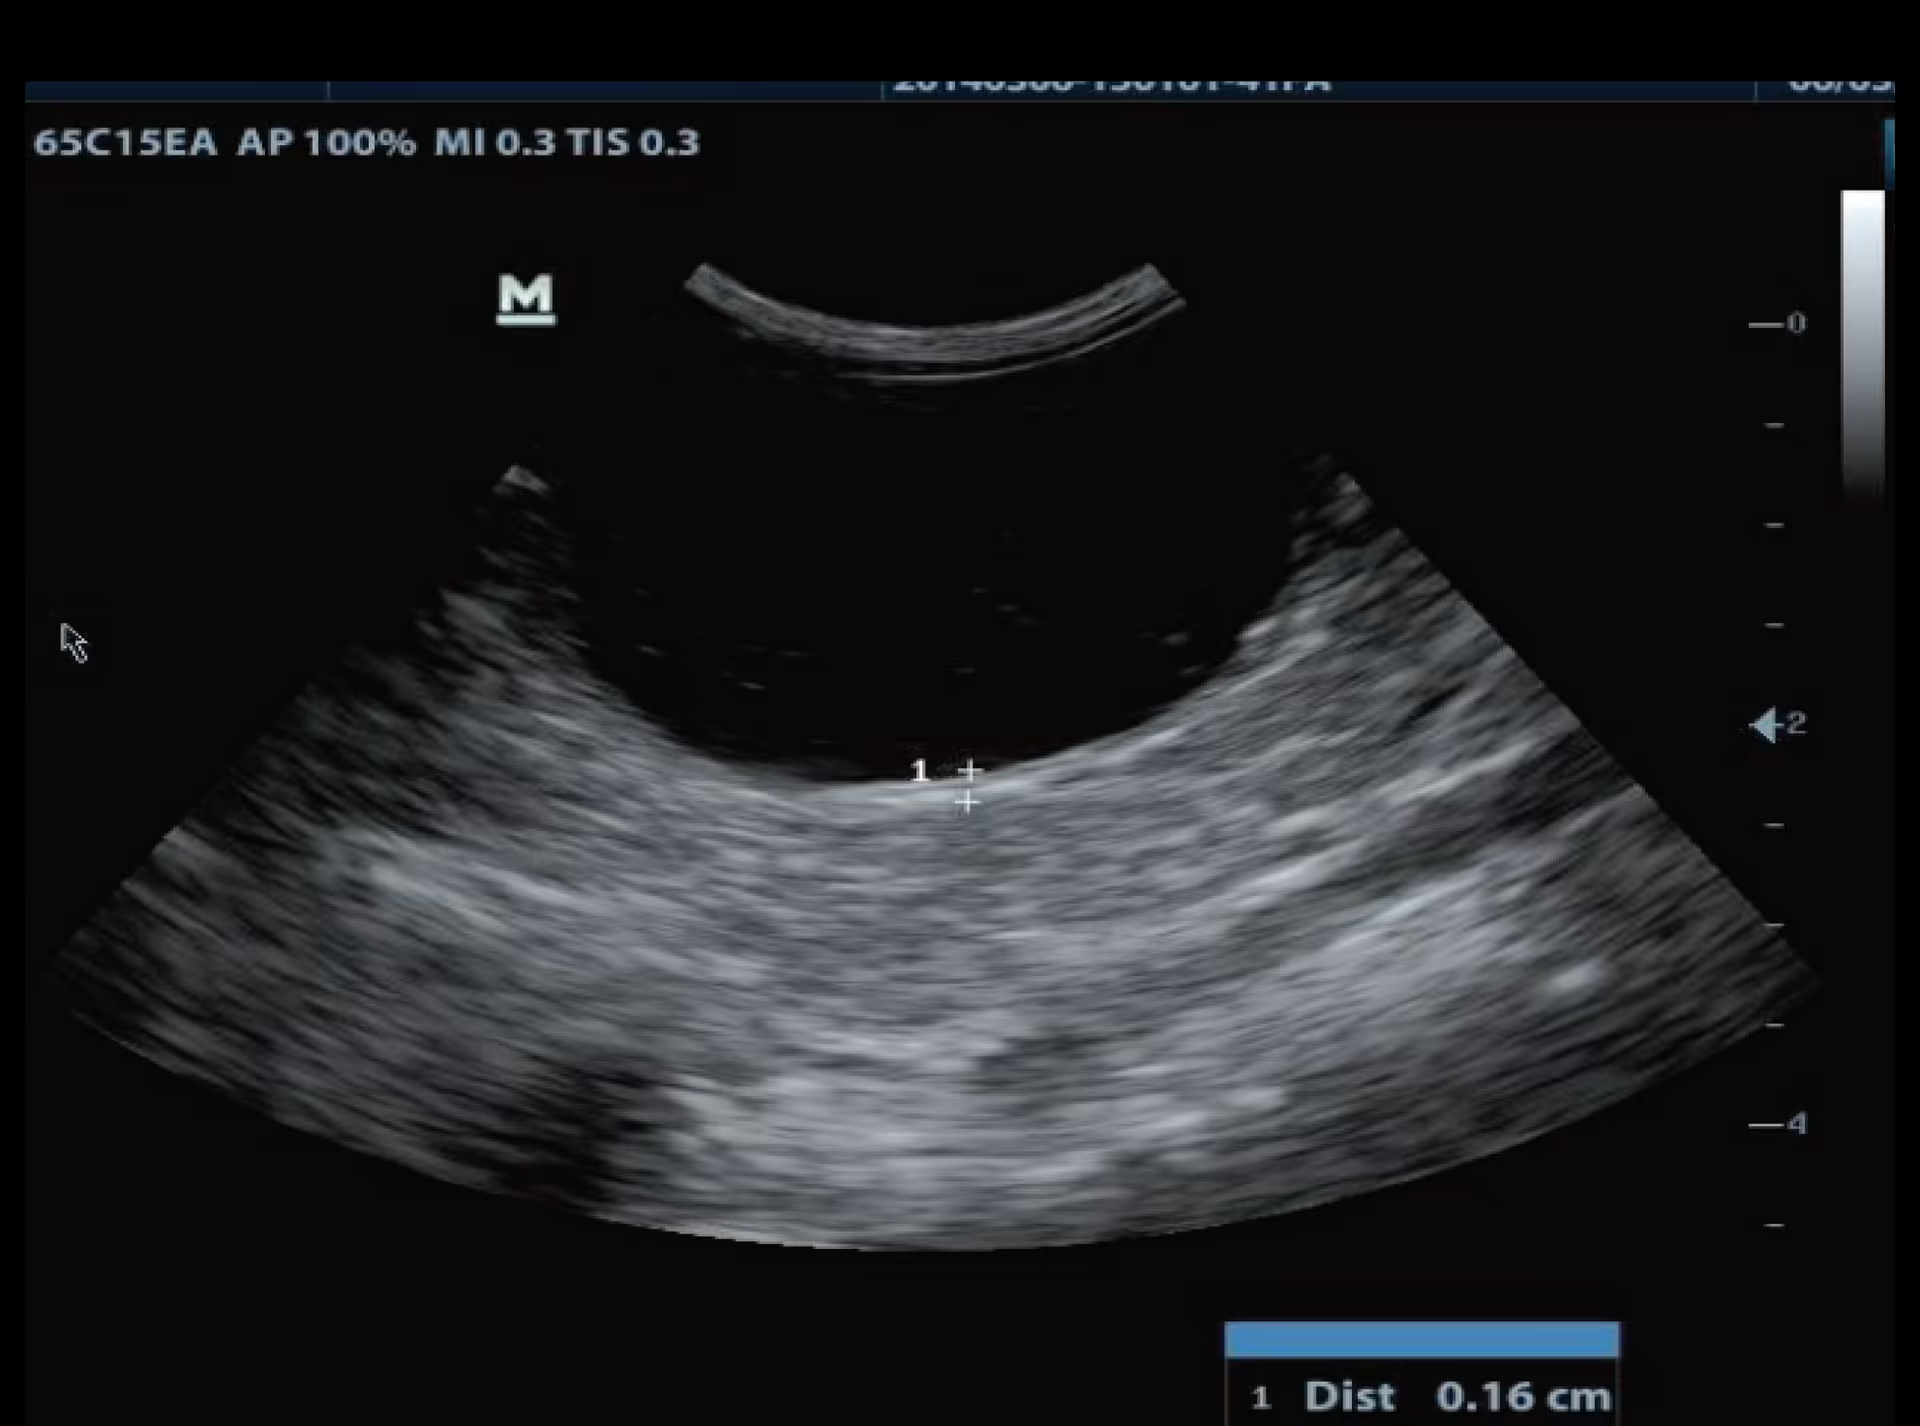

İdrar Kesesi, Köpek

İdrar Kesesi, Köpek